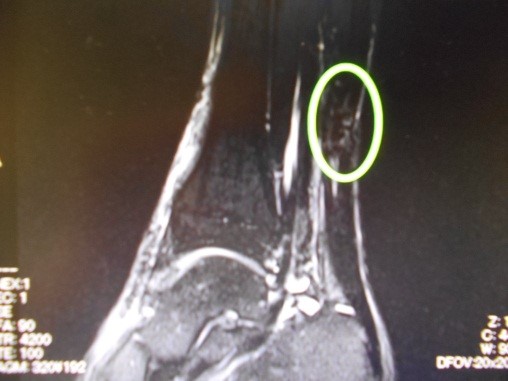

2017年12月に私事で非常に恐縮ですが、アキレス腱を断裂しました。

踵(かかと)の骨の上にあり、ふくらはぎの筋肉と踵をつなぐ腱のことです。踵骨腱(しょうこつけん)とも言います。「アキレス」の語源は、ギリシャ神話に登場する不死身の英雄アキレスの唯一の弱点で、戦争時にこの腱を弓で射抜かれ、命を落としたことから、この名がつけられたそうです。ランニングやジャンプなど、下肢を使って行う運動で重要な働きをします。アキレス腱には、普通に立ったり歩いたりする際にも負担がかかります。そのため準備運動が不十分だったり、運動不足の人がいきなり負荷をかけたりすると、炎症(アキレス腱炎)や、断裂(アキレス腱断裂)を起こしたりするので注意が必要です。アキレス腱は人体最大の腱で、約1トンの牽引力にも耐えるような強固な構造をしています。